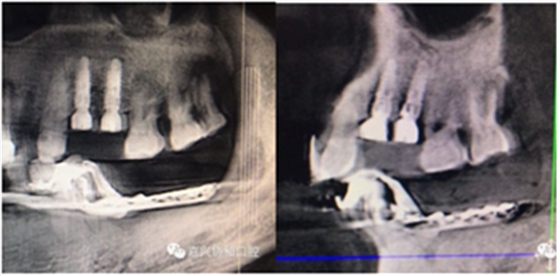

術(shù)后種植體位置與術(shù)前設(shè)計(jì)一致

3D數(shù)字化種植導(dǎo)板的臨床應(yīng)用,顛覆了以往以經(jīng)驗(yàn)判斷的粗放型的種植模式。

3D數(shù)字化種植導(dǎo)板的臨床應(yīng)用,是將種植牙精準(zhǔn)的種植于缺牙位點(diǎn),避免了臨近牙及重要器官的損傷、縮短了手術(shù)時(shí)間、減少了手術(shù)創(chuàng)傷,為缺失牙的咀嚼功能重建、外在形態(tài)恢復(fù)提供了保障。